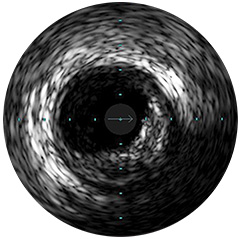

Digitale IVUS- Bildverarbeitung

Abbildung 1